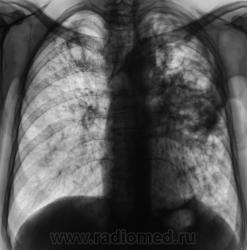

Произведены томограммы.

Хороший кавернозный туб.

А, не фиброзно-кавернозный?

Конечно ФКТ..) Классика жанра. Да зуб теперь долго лечить не будут((

Инфильтративный туберкулёз с обеих сторон